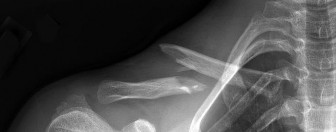

A 12-year-old elite Little League pitcher complains of progressively worsening pain in his throwing shoulder during the late cocking phase. Radiographs show widening and sclerosis of the proximal humeral physis. What is the primary pathophysiology of this condition (Little League Shoulder)?